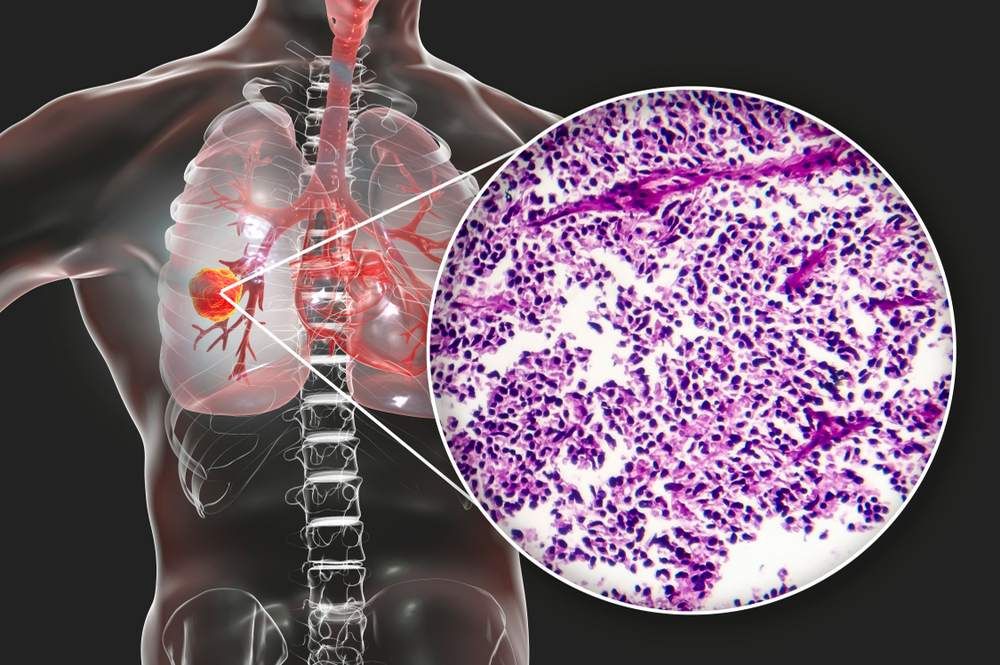

First Patient Dosed with Efti in Phase 3 Trial for Non-Small Cell Lung Cancer

The first patient has been dosed in the phase 3 trial TACTI-004, which will evaluate efti (eftilagimod alfa), a first in class MHC Class 2 agonist, in combination with anti-PD-1 therapy Keytruda (pembrolizumab) and chemotherapy as first-line treatment for …